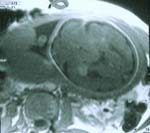

IRM :

- Masse cérébrale unilatérale hyperéchogène (même aspect que celui d’une hémorragie volumineuse ou de lésions d’infarctus hémorragique)

- Hydrocéphalie

- Déviation des structures de la ligne médiane